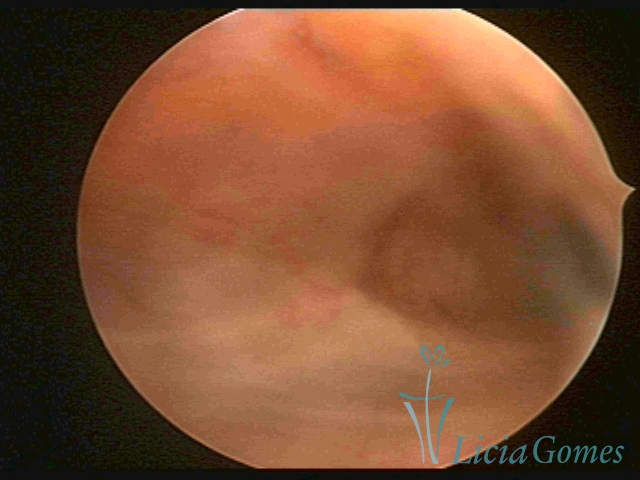

Primeira porção ou setor proximal ou setor inferior:

Durante a fase proliferativa, encontramos muco claro e cristalino pouco aderente à óptica. As criptas e as papilas apresentam-se um pouco edemaciadas e vascularizadas, micro vesicular, lembrando cachos de uva.